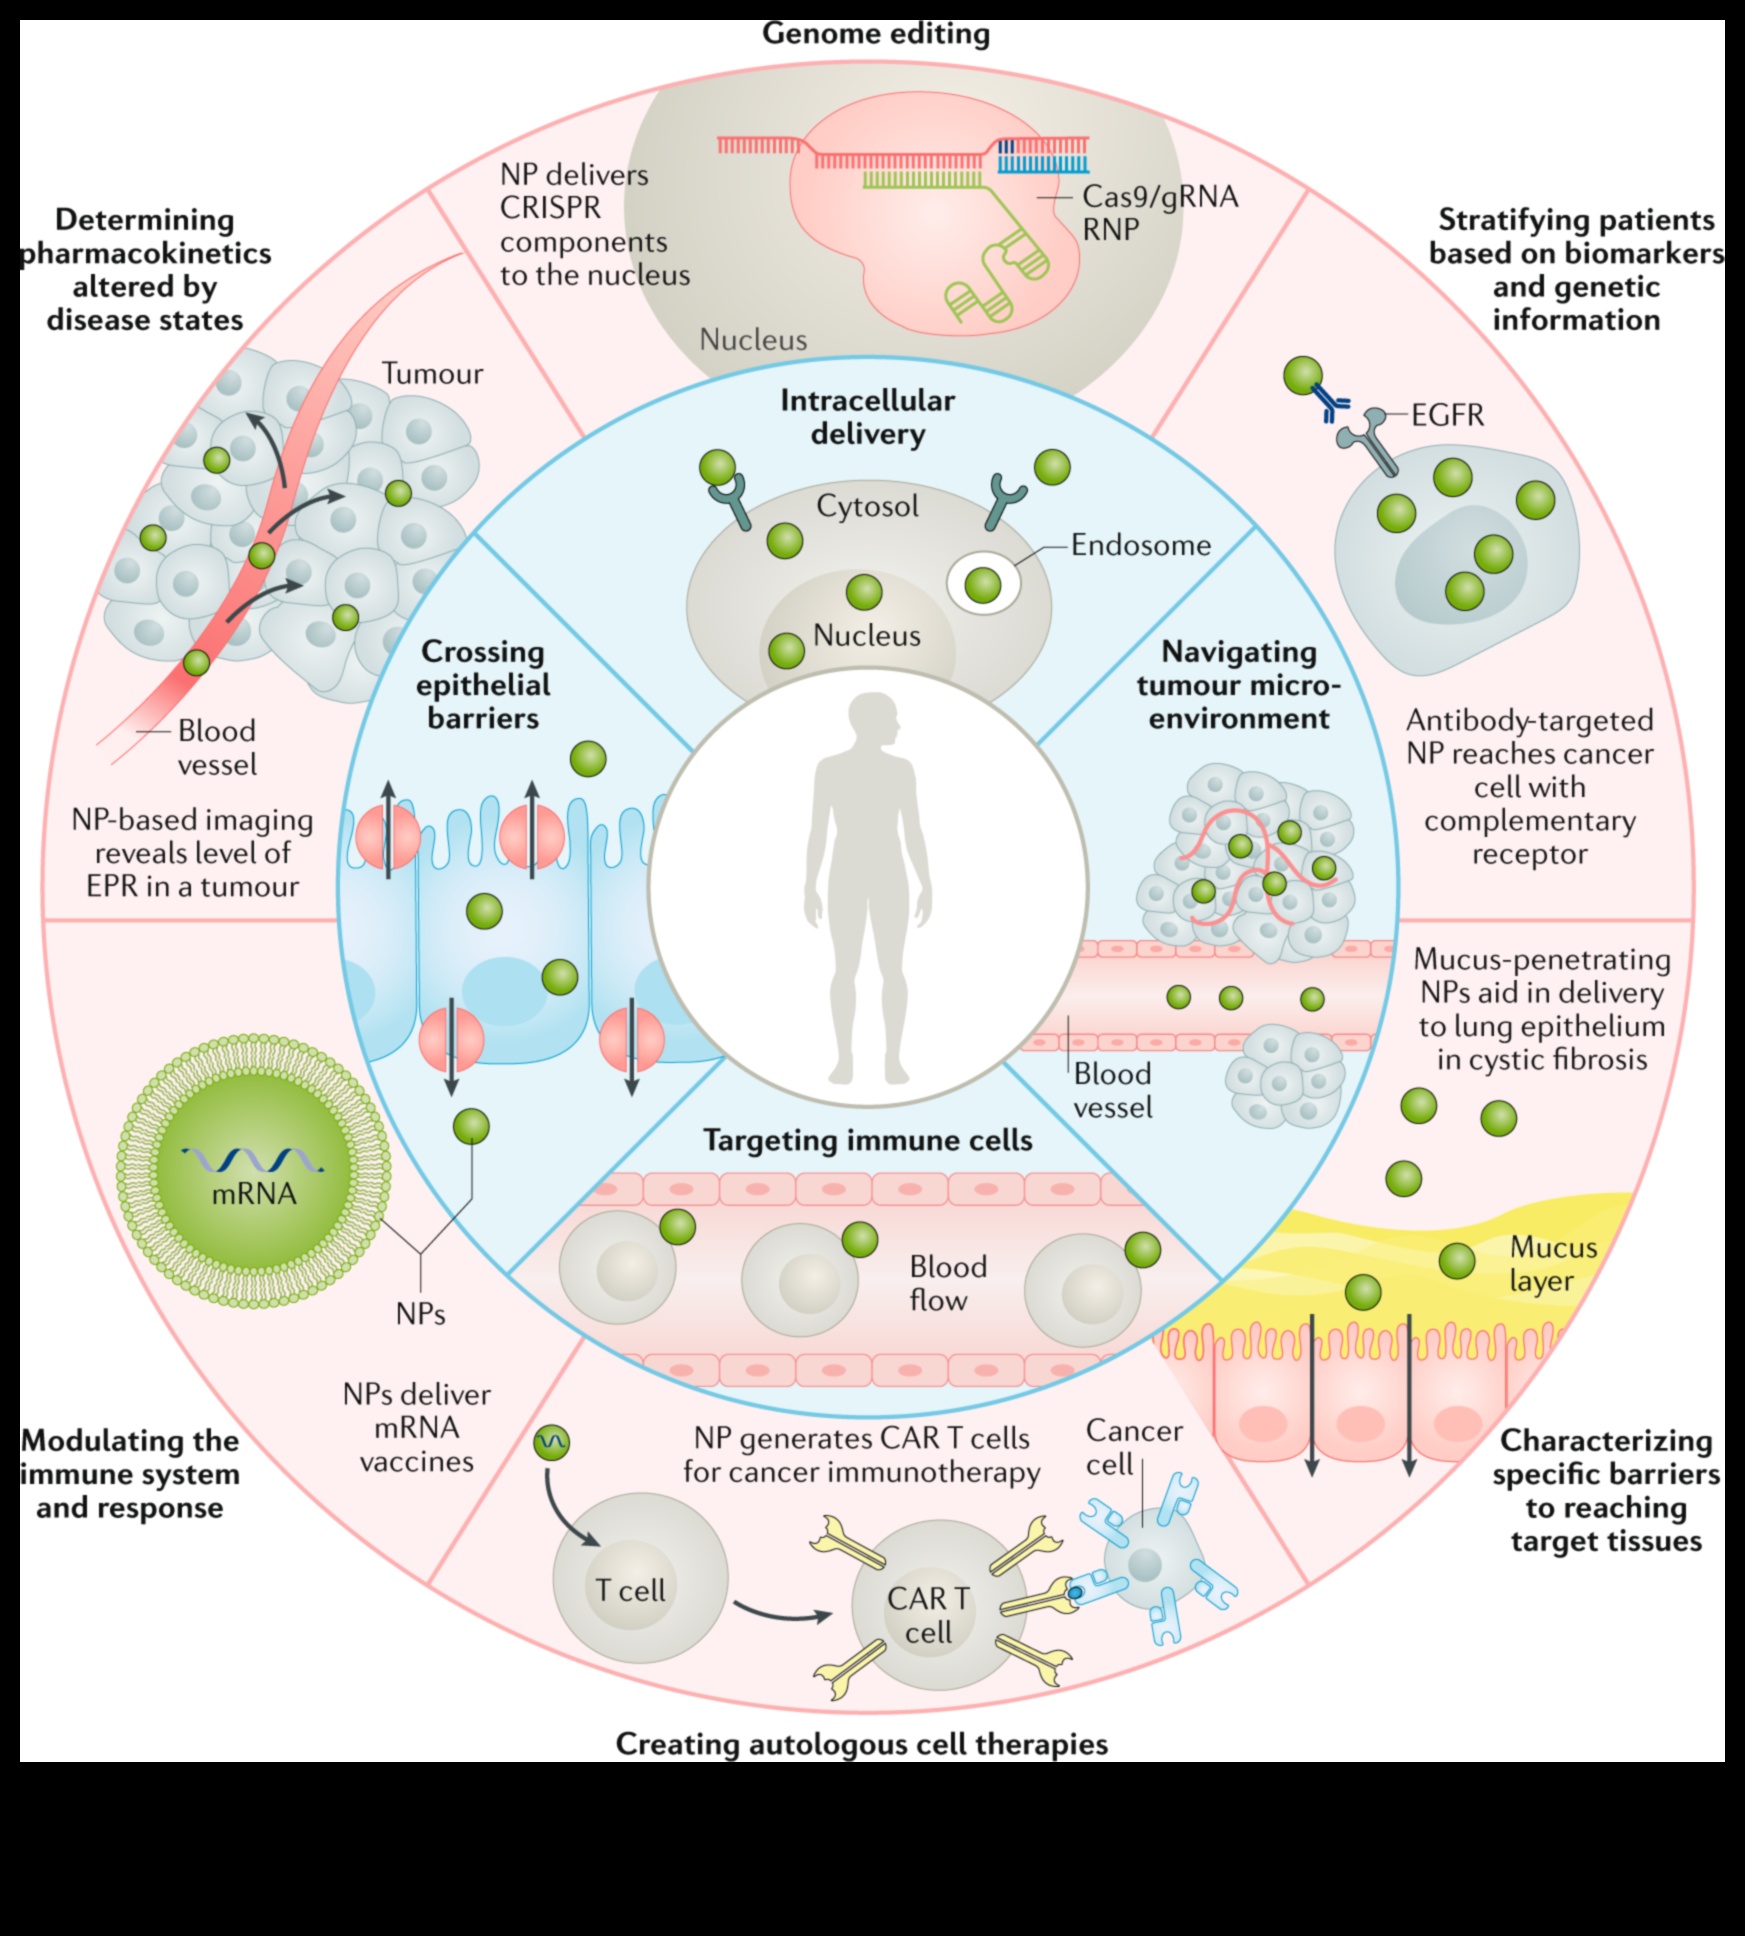

- Διεύρυνση τελευταίων ιατρικής και θεραπειών για ασθένειες.

Διεύρυνση τελευταίων ιατρικής και θεραπειών για ασθένειες.